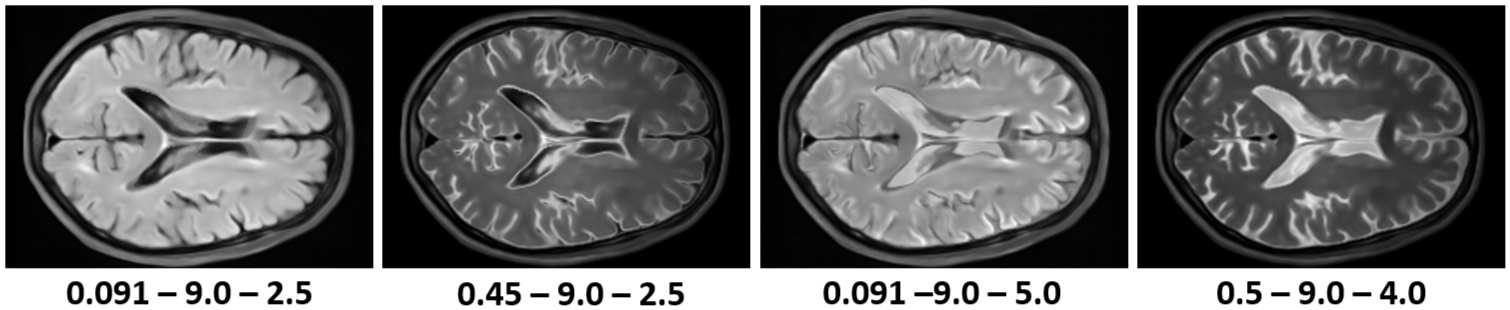

A key advantage of our physics-informed generative model over previous methods is the ability to synthesize modalities not present in the training data. Figure 3 shows how changes in the acquisition parameters affect the generated images using different signal models given a single tissue property map generated by our model. Although we can generate various novel MR contrasts, some acquisition parameter combinations can still lead to unrealistic images with bright backgrounds.